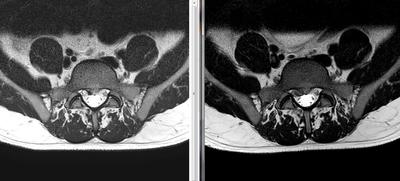

Not, i've done a NEW MRI (in the left is the MRI made in january, and in the right image is the MRI made in february 2016). The first was in january 2016, and this is february 2016.

The main difference in imaging is that the HDL got a little bigger, and also got to the point where the disc material got out and is "leaking" near the S1 right nerve root slightly compressing it.